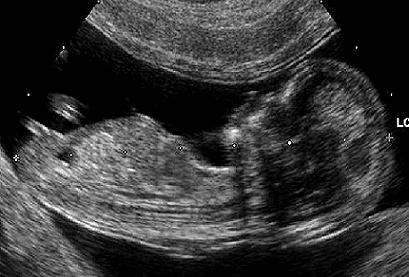

Comment, il y a dix ans, aurions-nous pu imaginer une telle dégringolade dans le respect de la famille et de l’enfant. En France, on bafoue encore davantage les droits de l’homme ! Mgr Aupetit, archevêque de Paris ne mâche pas ses mots : « Je le répète une fois encore : l’enfant est un don à recevoir, pas un dû à fabriquer. L’absence d’un père est une blessure que l’on peut subir, mais il est monstrueux de l’infliger volontairement. »